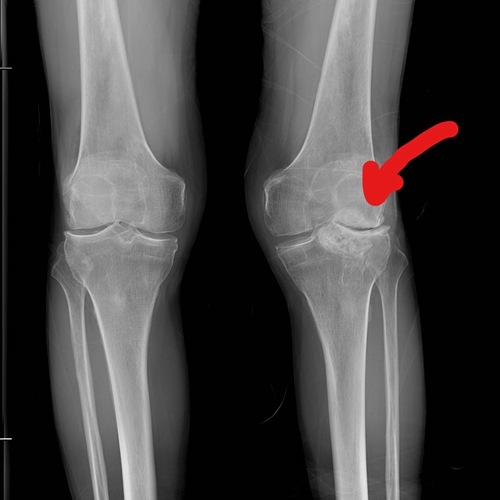

术前检查

经检查,提示其左膝关节外侧已完全磨损,并伴有较大游离体,常卡在关节里,引发疼痛与活动受限。知道自己的情况后,张老伯非常担心:“医生,我这膝盖……是不是非得‘大动干戈’才行?我听说全关节置换手术创伤大,恢复也慢,我这把年纪了,实在有点害怕。”